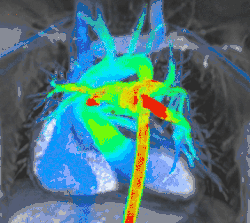

4D flow CMR

Conventional phase contrast imaging can be extended by applying flow-sensitive gradients in 3 orthogonal planes within a 3D volume throughout the cardiac cycle. Such 4D imaging encodes the velocity of flowing blood at each voxel in the volume enabling fluid dynamics to be visualised using specialist software. Applications are in complex congenital heart disease and for research into cardiovascular flow characteristics - however it is not in routine clinical use due to the complexity of post-processing and relatively long acquisition times.[26]

4D flow models. Intra- and extracardiac flow is visualised in a time-resolved 4D volume encompassing the heart and great vessels. Left: Flow velocity. Centre: Streamlines. Right: Flow vectors.